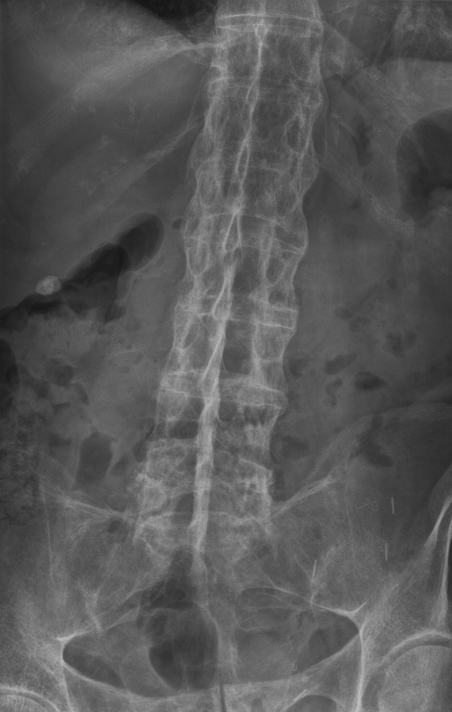

Example 3

Diagnosis

Ureteric Stones